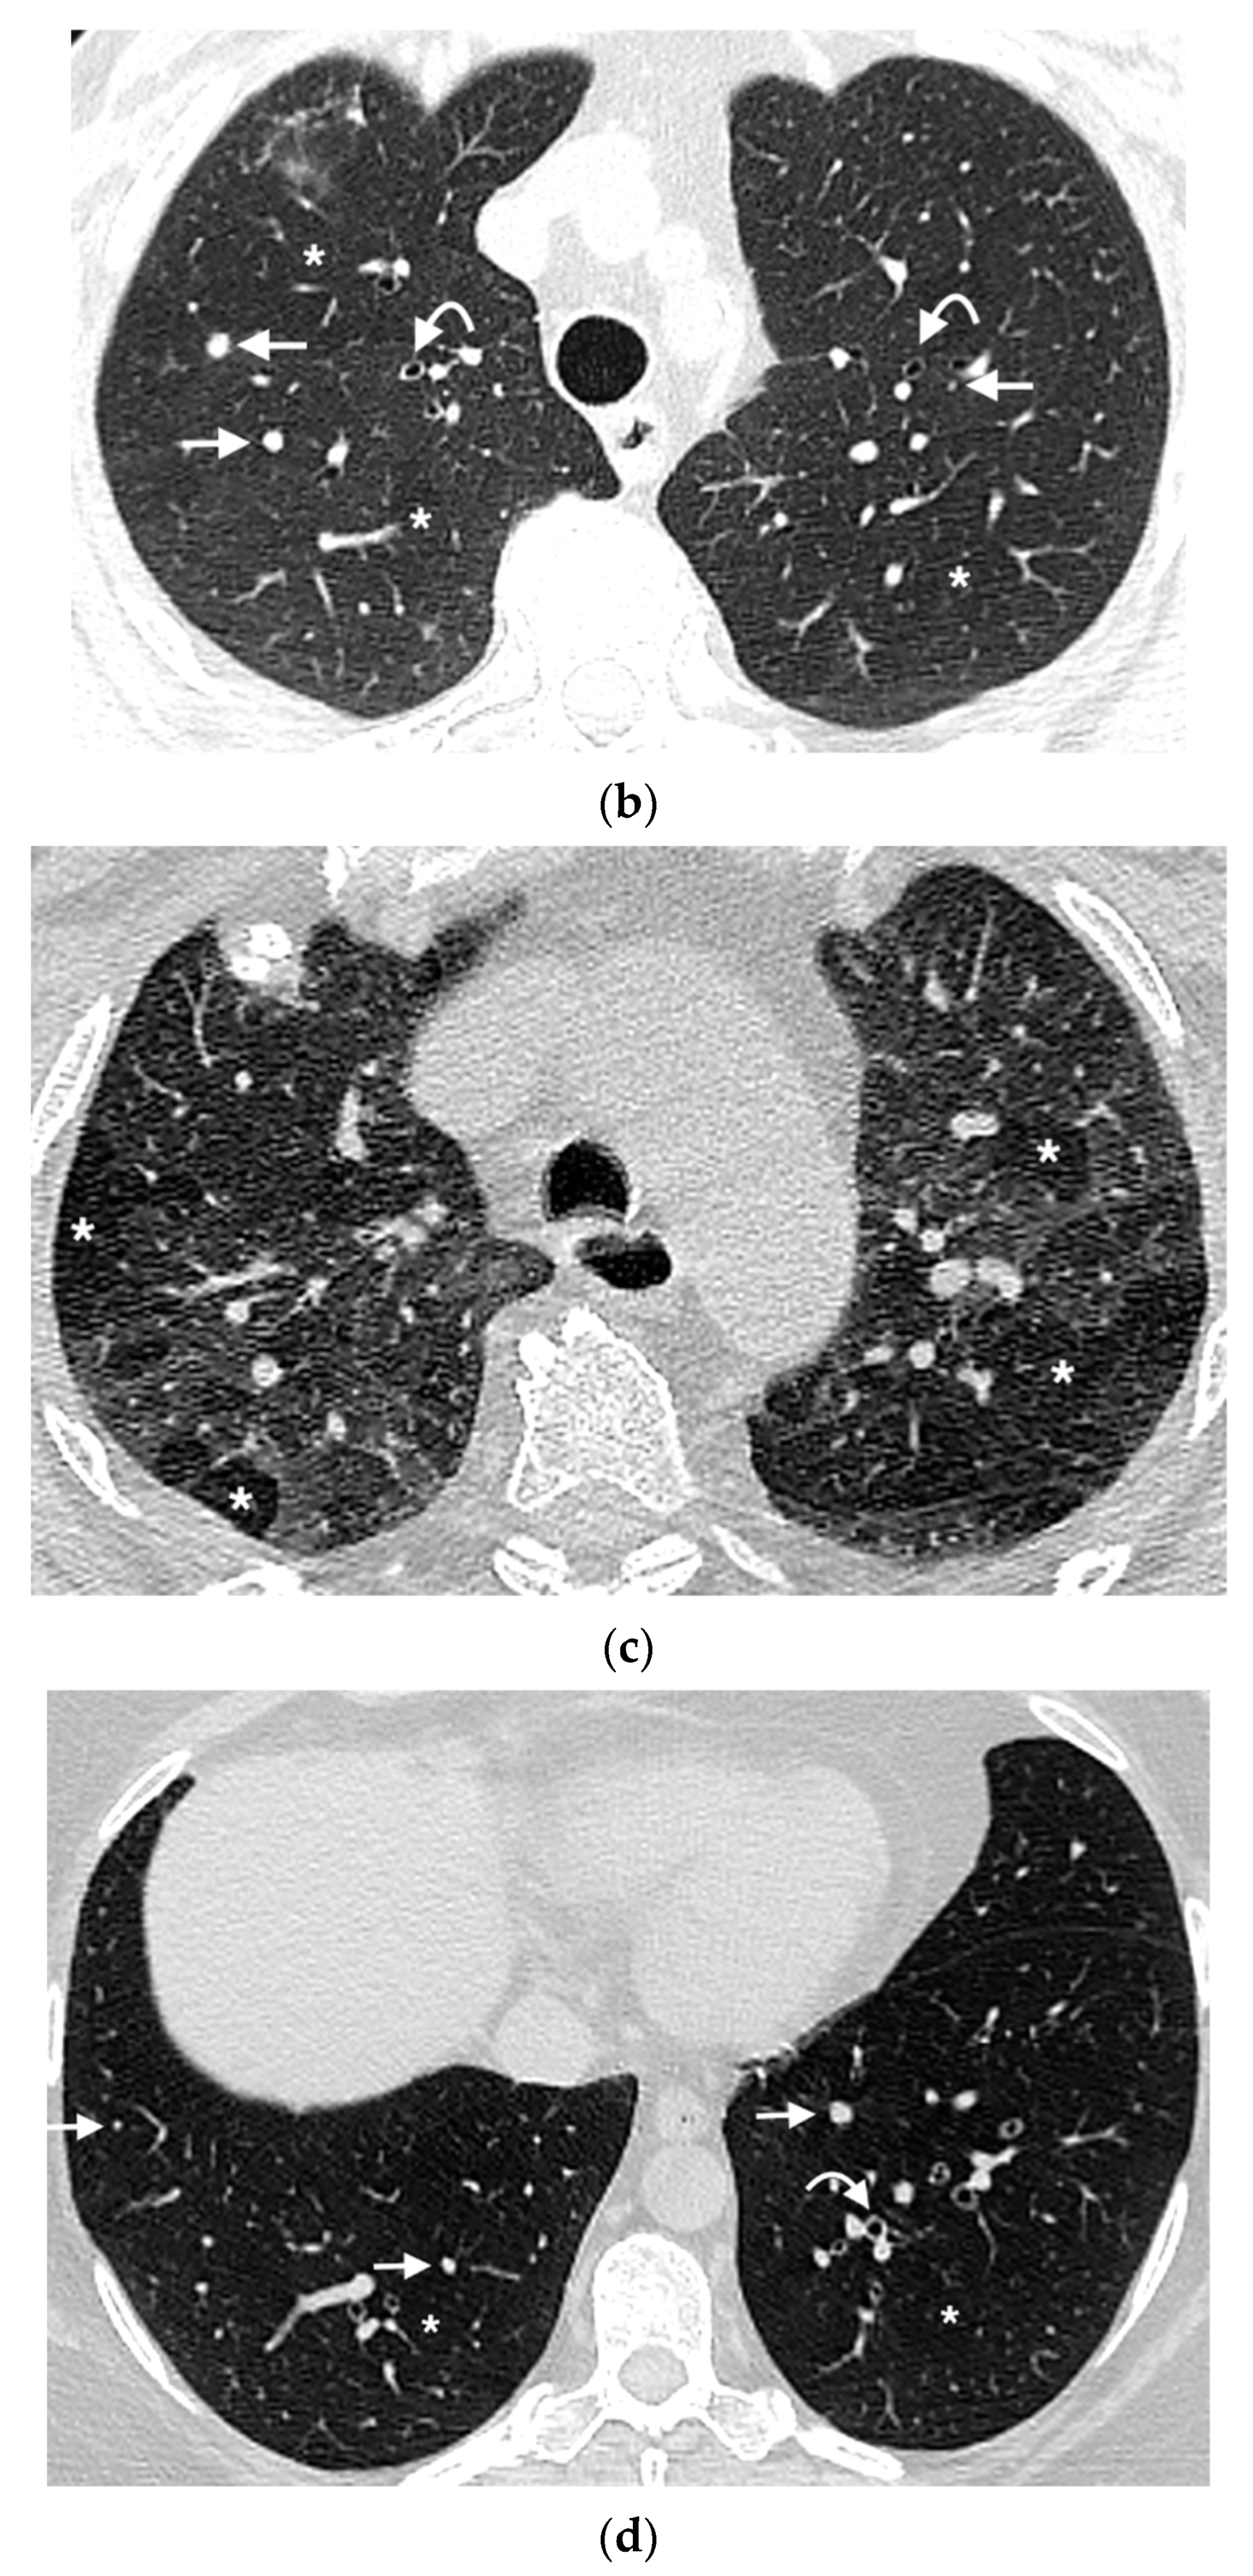

:1. Introduction

3. Results

3.3. Mosaic Attenuation

3.4. Nodule Characteristics